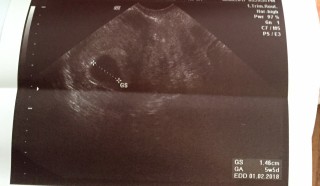

年明けから何となく熱っぽさが続いていて、検査薬を試したらすぐに陽性反応が! 予約を取って病院で診て貰うと、妊娠5週目との事。 胎嚢は7.8mmと平均より小さいとの事。このまま育たない可能性もあるかもしれないと言われたけど、まだ初診ですからね。2回目以降の診察で言われるならまだしも... 小さくてもちゃんと生きてます。 次回の健診が楽しみです。